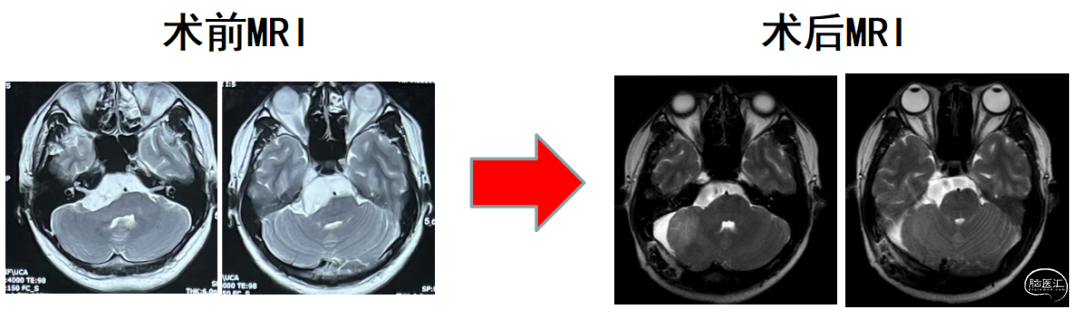

术后MRI